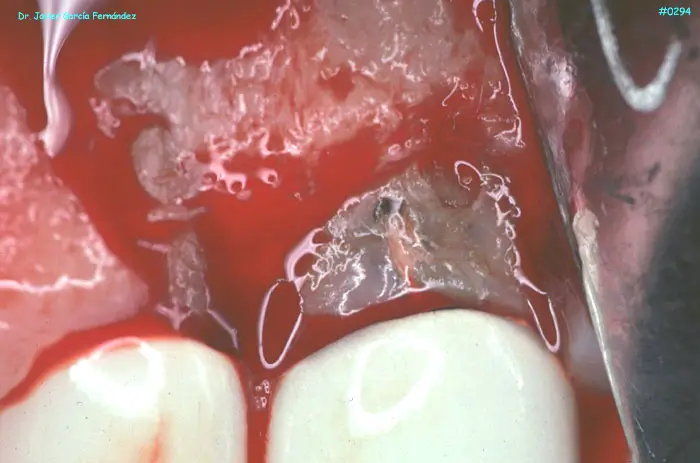

ATLAS DE CIRUGIA PERIODONTAL